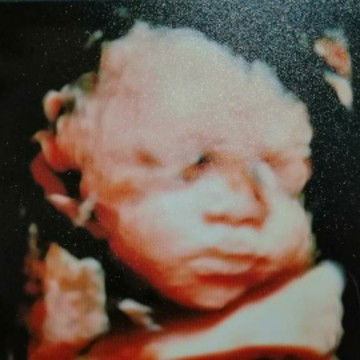

My Baby

Hi mommies! I'm 32 weeks preggy. Kkapa-ultrasound ko lng ng 3d last Sat. Ang tagal ng hinintay namin pero worth it dahil nakita na namin ang itsura nya. Yung ikaw ang nagdala ng 9months tapos kamukhang kamukha ng tatay hahhaha! Tanong ko lang, okay lang ba na 3d ultrasound lang? hindi na po ba ulit ako magppa ultrasound bago manganak?